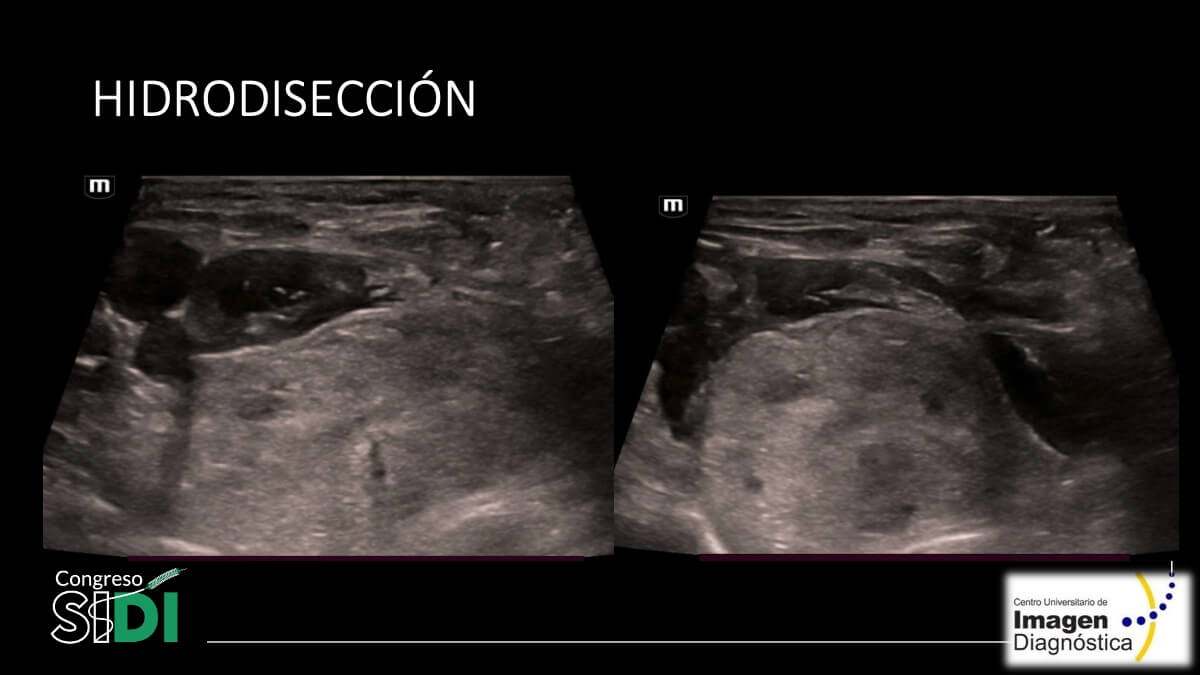

PE_049_Crystyan M. Acosta-David_06